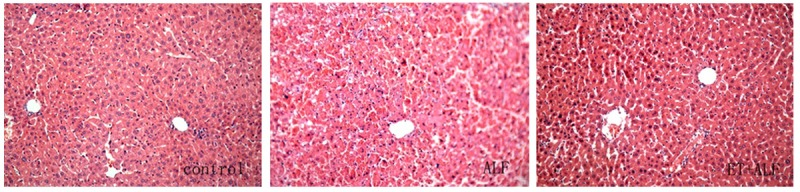

随后对ALF模型的肝损伤及细胞因子释放进行了研究。通过H&E染色观察肝组织病理学变化,对照组肝脏组织学表现正常(图2)。然而,ALF组与ET+ALF组的肝组织均呈现不同程度的损伤,且存在显著差异。ALF组肝脏组织出现严重损伤,表现为肝小叶结构破坏、肝索断裂及大量浸润性炎症细胞(以单核细胞和淋巴细胞为主),同时可观察到坏死和凋亡现象(图2)。而ET+ALF组肝损伤程度较轻,肝细胞坏死较少,肝小叶结构清晰可见,且浸润性炎症细胞数量较少(图2)。此外,我们还检测了肝损伤的血清标志物。如表1所示,腹腔注射D-GalN/LPS后,ALF组和ET+ALF组的ALT、AST及TBiL水平均升高。但ALF组各时间点的ALT、AST和TBiL升高幅度均显著高于ET+ALF组(p<0.05)。值得注意的是,两组的ALT和AST水平均在注射后12小时达到峰值,而TBiL水平则在注射后持续升高。除减轻肝损伤指标外,LPS预处理还显著降低了炎症介质(TNF-α和IL-6)的产生(表1)。虽然在ALF和ET+ALF组中注射D-GalN/LPS后,TNF-α和IL-6的表达均有所增加,但在实验的每个时间点,ET+ALF组大鼠的TNF-α和IL-6水平均显著低于ALF组(P<0.05)。

图2.肝组织切片的组织病理学检查结果。